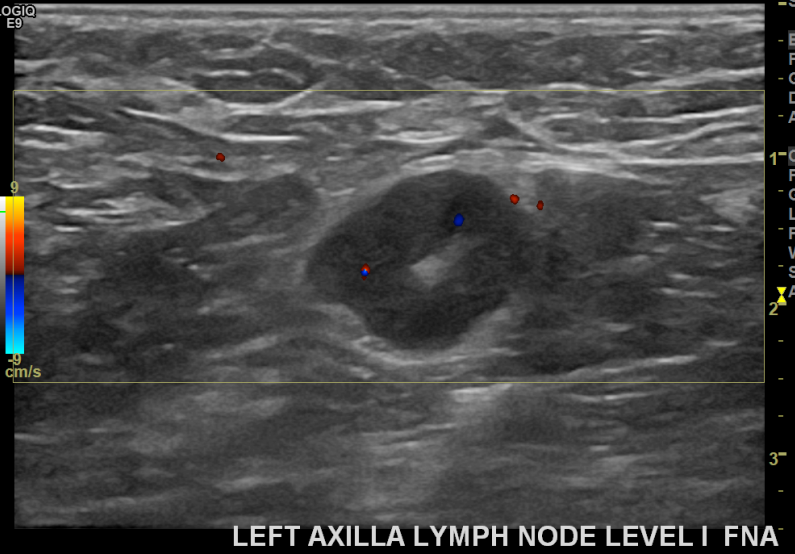

상기환자 외부검사이상으로  좌측조직검사를위해  내원하신 40대초반 여성분으로

좌측 조직검사 시행해 침윤성암으로 진단되었습니다